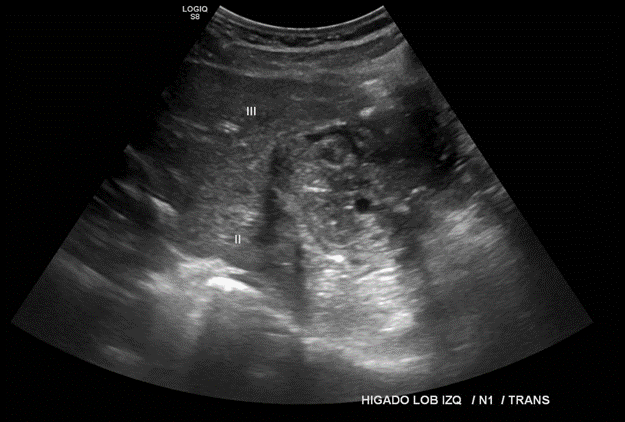

En hígado se visualizan 3 imágenes nodulares, heterogéneas parcialmente calcificadas periféricamente, la de mayor tamaño encuentra en Lob hepático izquierdo cuyas dimensiones abarcan el segmento 2 y 3, otra se ubica entre el límite de LHD e LHI con mayor énfasis en LHI y la última en LHD en segmento 7, todas sin señal categórica al Doppler, sugerente de quistes hidatídicos calcificados de larga data.

Formaciones de aspecto quístico complejo hepáticas, y otra en pared de flanco izquierdo; las que plantean diagnóstico de hidatidosis. Correlacionar como tomografía computada.